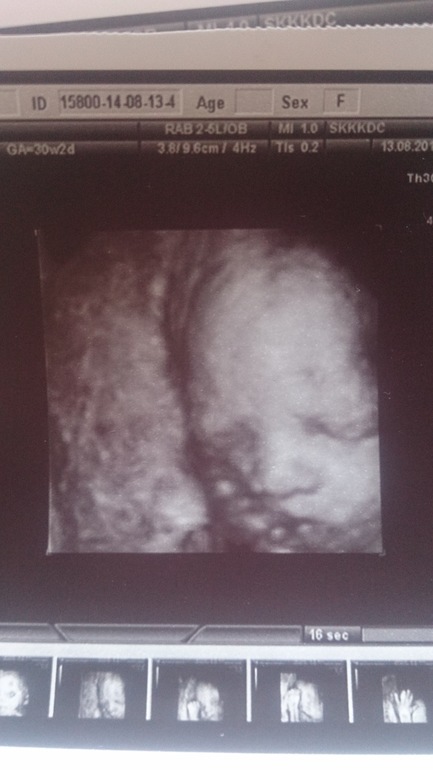

наше третье плановое 3д узи))

УЗИ, КТГ, доплерЯ под огромным впечатлением))))) Она такая хорошенькая, наша крошечка)) Муж в ступоре сидел)) Но огорчило то, что доча села на попу и намотала пуповину...((( Страшно, что теперь делать? Узист сказала, что упражнения нежелательно делать, если есть обвитие, что теперь? Кесарево? Весит мы 1650 в 30 недель и 2 дня. А сколько весили ваши малыши на таком сроке и сколько родились?